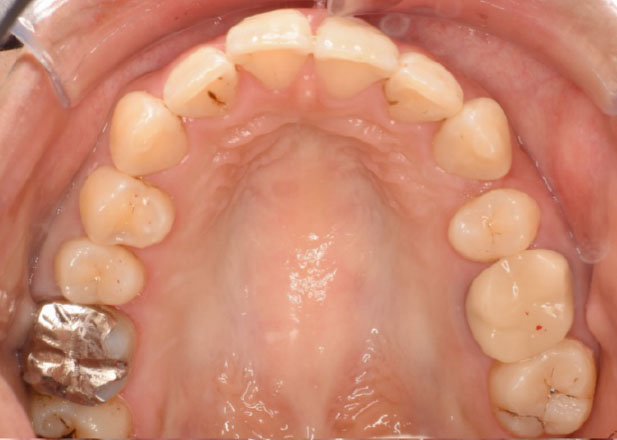

治療後

マウスピース矯正 マウスピース矯正 マウスピース矯正

口腔内写真